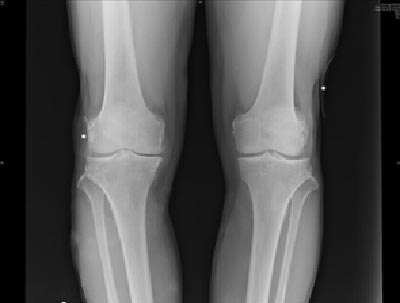

(图:李先生治疗后的双膝关节X光)

接受第一个疗程治疗后,李先生感觉各个关节疼痛减轻,双膝关节肿胀有所消退,细小痛风溶解,双足关节肤色恢复正常,关节僵硬缓解不少。

接受第二个疗程治疗后,李先生的双手臂肌肉疼痛消失,双膝关节肿痛缓解,按压还有轻微疼痛,能慢慢蹲起,双足第一跖趾关节痛风石溶解变小,发作次数越来越少。

接受第三个疗程治疗后,李先生的各个关节红肿痛消失,痛风石全溶解,骨质好转,关节转动灵活,蹲起自如。李先生到院复查,数据显示各项指标均在正常范围内,无异常症状迹象。